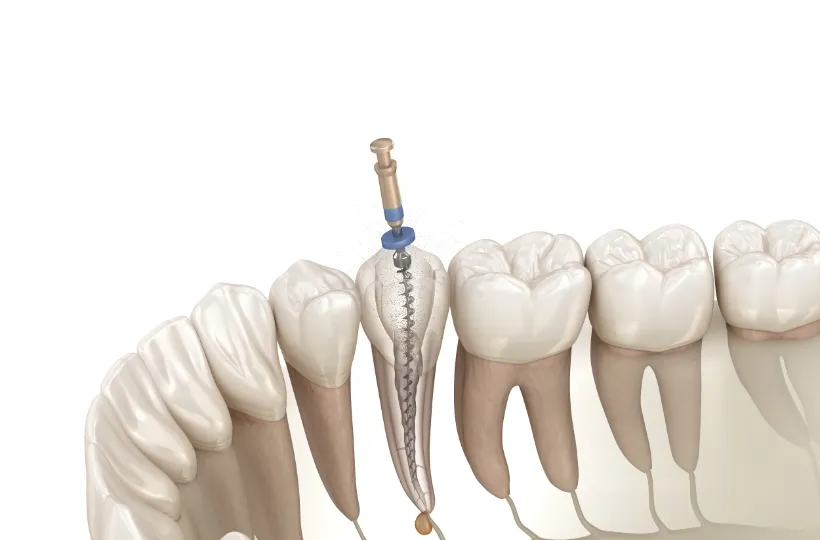

精密根管治療

神経まで進行して炎症を起こしている虫歯に対して行なう治療法になります。感染した神経を取り除き、しっかりと洗浄・消毒し、最後に薬剤を詰めて被せ物を装着します。

精密根管治療 -